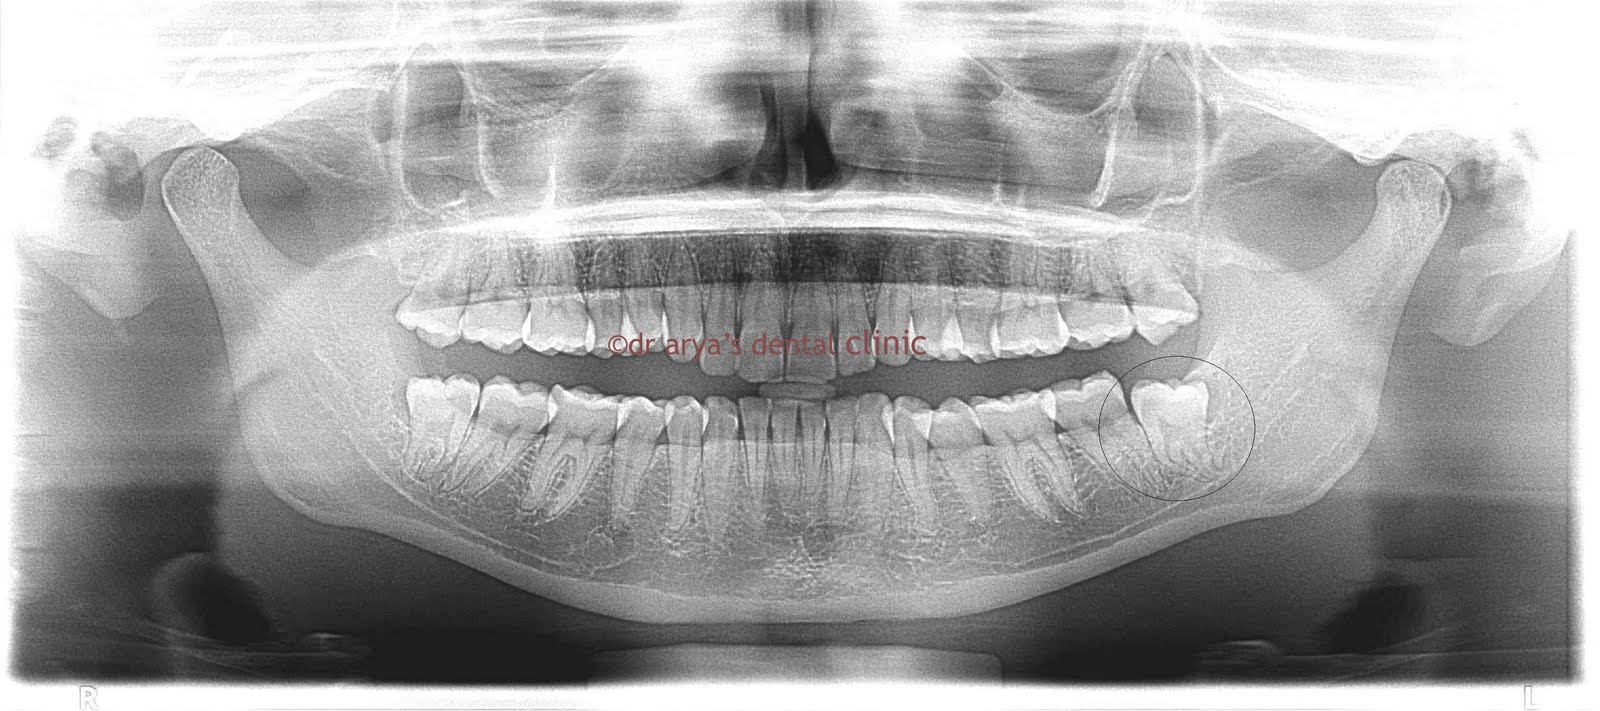

First things first - the dentist will probably want to see an x-ray of the tooth. In all probability you may have to take an OPG ( which is basically an xray of all the teeth together)

If the tooth looks like it can erupt naturally - the dentist will aid in its eruption by cutting the gum tissue which is covering it and preventing it from coming out.

However if the position of the tooth looks as if its not going to ever erupt in a normal position or if the tooth is impinging on the tooth in front of it and damaging it the dentist will ask you to go in for a Disimpaction procedure.